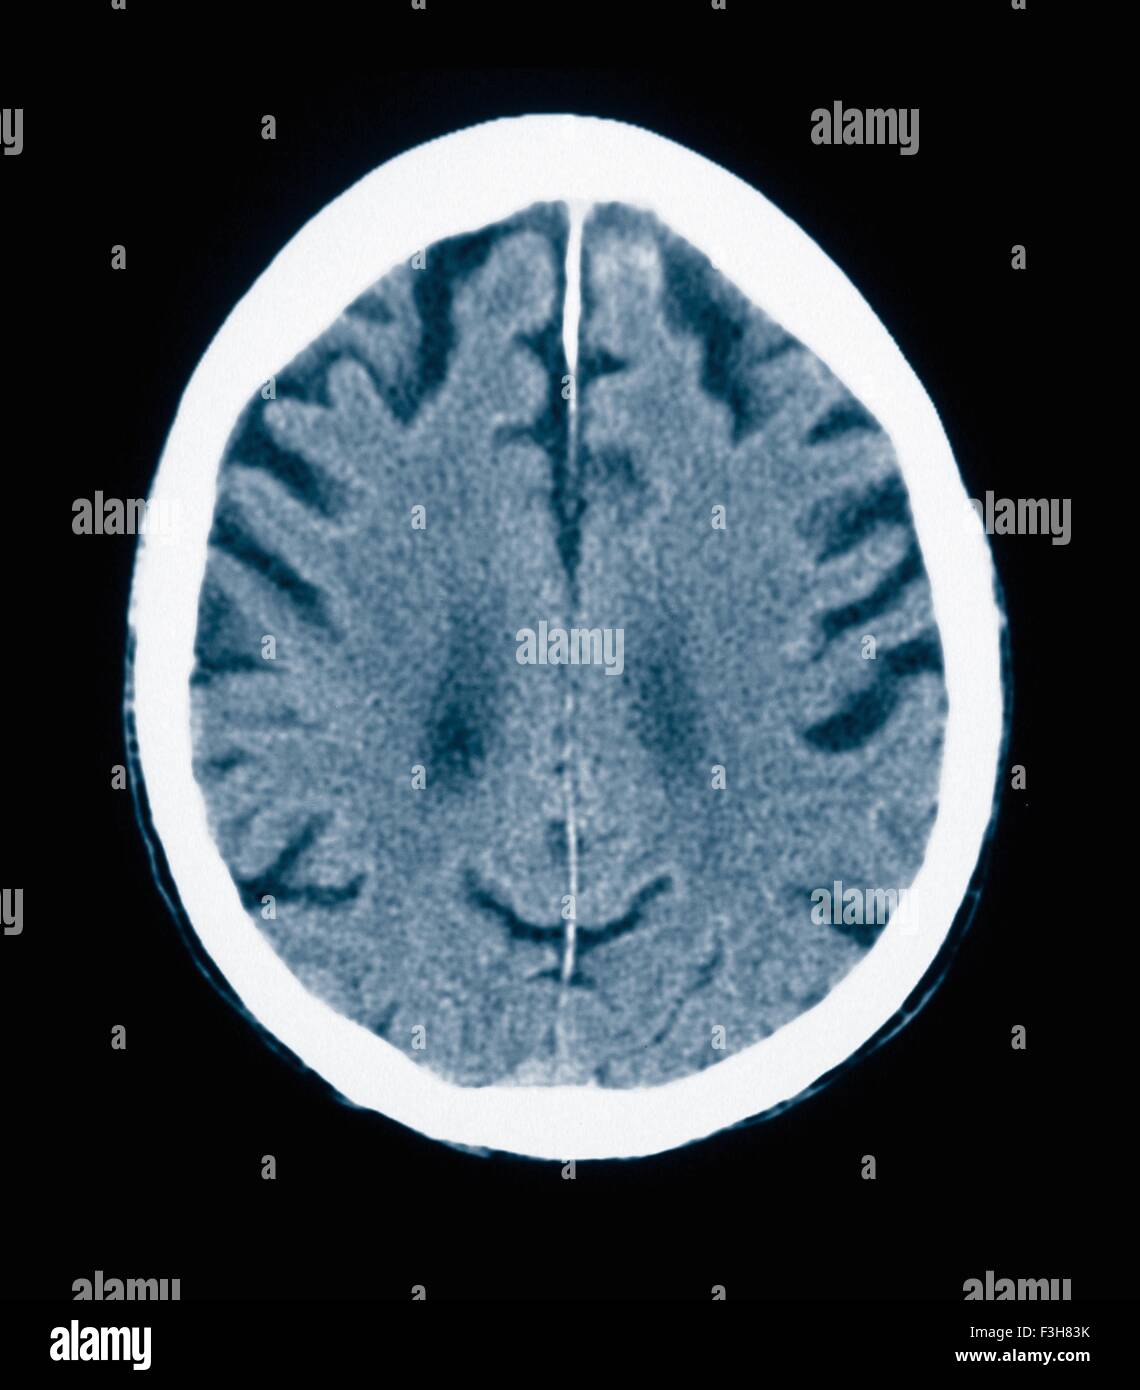

CT scan 84 ans homme à la maladie d'Alzheimer. La TDM montre l'atrophie du cerveau avec de petites et grandes circonvolutions sulci Banque D'Imageshttps://www.alamyimages.fr/image-license-details/?v=1https://www.alamyimages.fr/photo-image-ct-scan-84-ans-homme-a-la-maladie-d-alzheimer-la-tdm-montre-l-atrophie-du-cerveau-avec-de-petites-et-grandes-circonvolutions-sulci-88275359.html

CT scan 84 ans homme à la maladie d'Alzheimer. La TDM montre l'atrophie du cerveau avec de petites et grandes circonvolutions sulci Banque D'Imageshttps://www.alamyimages.fr/image-license-details/?v=1https://www.alamyimages.fr/photo-image-ct-scan-84-ans-homme-a-la-maladie-d-alzheimer-la-tdm-montre-l-atrophie-du-cerveau-avec-de-petites-et-grandes-circonvolutions-sulci-88275359.htmlRFF3H83B–CT scan 84 ans homme à la maladie d'Alzheimer. La TDM montre l'atrophie du cerveau avec de petites et grandes circonvolutions sulci

CT scan 84 ans homme à la maladie d'Alzheimer. La TDM montre l'atrophie du cerveau avec de petites et grandes circonvolutions sulci Banque D'Imageshttps://www.alamyimages.fr/image-license-details/?v=1https://www.alamyimages.fr/photo-image-ct-scan-84-ans-homme-a-la-maladie-d-alzheimer-la-tdm-montre-l-atrophie-du-cerveau-avec-de-petites-et-grandes-circonvolutions-sulci-88275360.html

CT scan 84 ans homme à la maladie d'Alzheimer. La TDM montre l'atrophie du cerveau avec de petites et grandes circonvolutions sulci Banque D'Imageshttps://www.alamyimages.fr/image-license-details/?v=1https://www.alamyimages.fr/photo-image-ct-scan-84-ans-homme-a-la-maladie-d-alzheimer-la-tdm-montre-l-atrophie-du-cerveau-avec-de-petites-et-grandes-circonvolutions-sulci-88275360.htmlRFF3H83C–CT scan 84 ans homme à la maladie d'Alzheimer. La TDM montre l'atrophie du cerveau avec de petites et grandes circonvolutions sulci

CT scan 84 ans homme à la maladie d'Alzheimer. La TDM montre l'atrophie du cerveau avec de petites et grandes circonvolutions sulci Banque D'Imageshttps://www.alamyimages.fr/image-license-details/?v=1https://www.alamyimages.fr/photo-image-ct-scan-84-ans-homme-a-la-maladie-d-alzheimer-la-tdm-montre-l-atrophie-du-cerveau-avec-de-petites-et-grandes-circonvolutions-sulci-88275369.html

CT scan 84 ans homme à la maladie d'Alzheimer. La TDM montre l'atrophie du cerveau avec de petites et grandes circonvolutions sulci Banque D'Imageshttps://www.alamyimages.fr/image-license-details/?v=1https://www.alamyimages.fr/photo-image-ct-scan-84-ans-homme-a-la-maladie-d-alzheimer-la-tdm-montre-l-atrophie-du-cerveau-avec-de-petites-et-grandes-circonvolutions-sulci-88275369.htmlRFF3H83N–CT scan 84 ans homme à la maladie d'Alzheimer. La TDM montre l'atrophie du cerveau avec de petites et grandes circonvolutions sulci

CT scan 84 ans homme à la maladie d'Alzheimer. La TDM montre l'atrophie du cerveau avec de petites et grandes circonvolutions sulci Banque D'Imageshttps://www.alamyimages.fr/image-license-details/?v=1https://www.alamyimages.fr/photo-image-ct-scan-84-ans-homme-a-la-maladie-d-alzheimer-la-tdm-montre-l-atrophie-du-cerveau-avec-de-petites-et-grandes-circonvolutions-sulci-88275367.html

CT scan 84 ans homme à la maladie d'Alzheimer. La TDM montre l'atrophie du cerveau avec de petites et grandes circonvolutions sulci Banque D'Imageshttps://www.alamyimages.fr/image-license-details/?v=1https://www.alamyimages.fr/photo-image-ct-scan-84-ans-homme-a-la-maladie-d-alzheimer-la-tdm-montre-l-atrophie-du-cerveau-avec-de-petites-et-grandes-circonvolutions-sulci-88275367.htmlRFF3H83K–CT scan 84 ans homme à la maladie d'Alzheimer. La TDM montre l'atrophie du cerveau avec de petites et grandes circonvolutions sulci